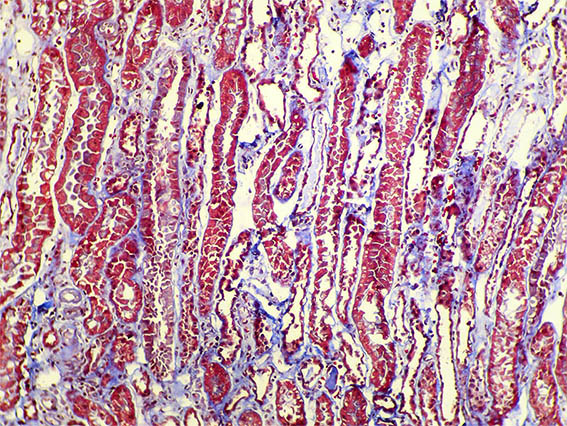

Figura 2. Tricrómico de Masson, X200.